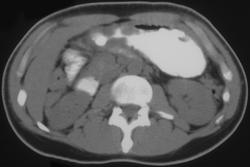

Leiomyosarcoma